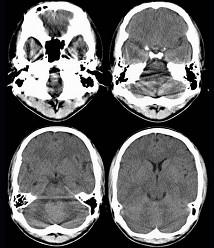

问题 男,16岁,头痛、呕吐10天,CT检查如图所示,最可能的诊断为()

选项 A.脑膜瘤 B.髓母细胞瘤 C.室管膜瘤 D.脑血管瘤 E.血管母细胞瘤

答案 B